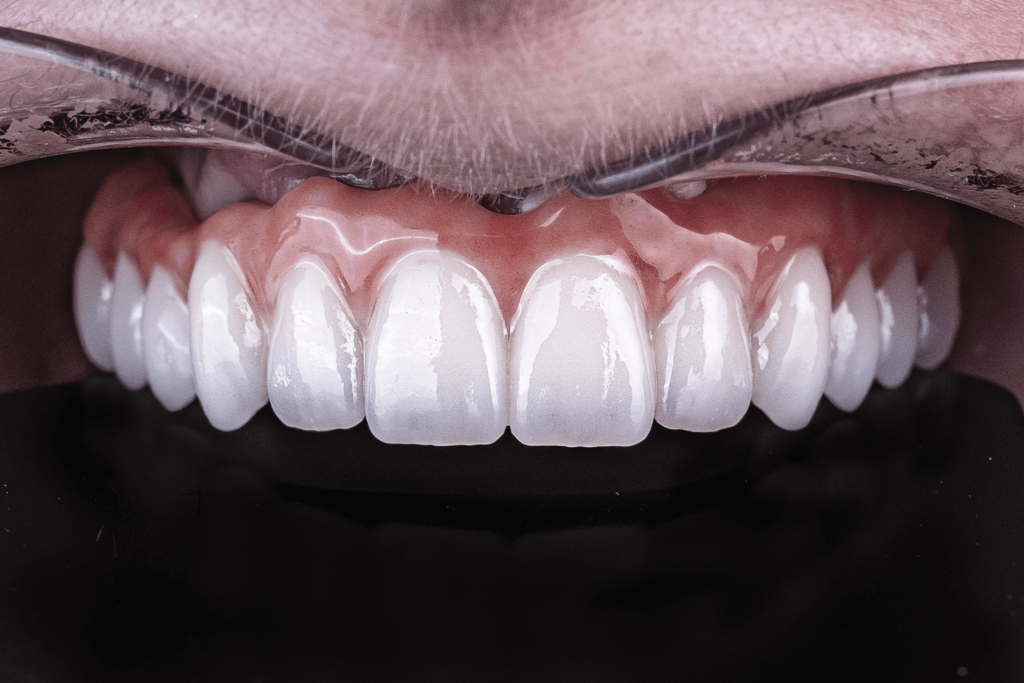

- Протезирование выполнить цельнолитым зубным протезом из диоксида циркония

- Зубной протез усилить титановой балкой.